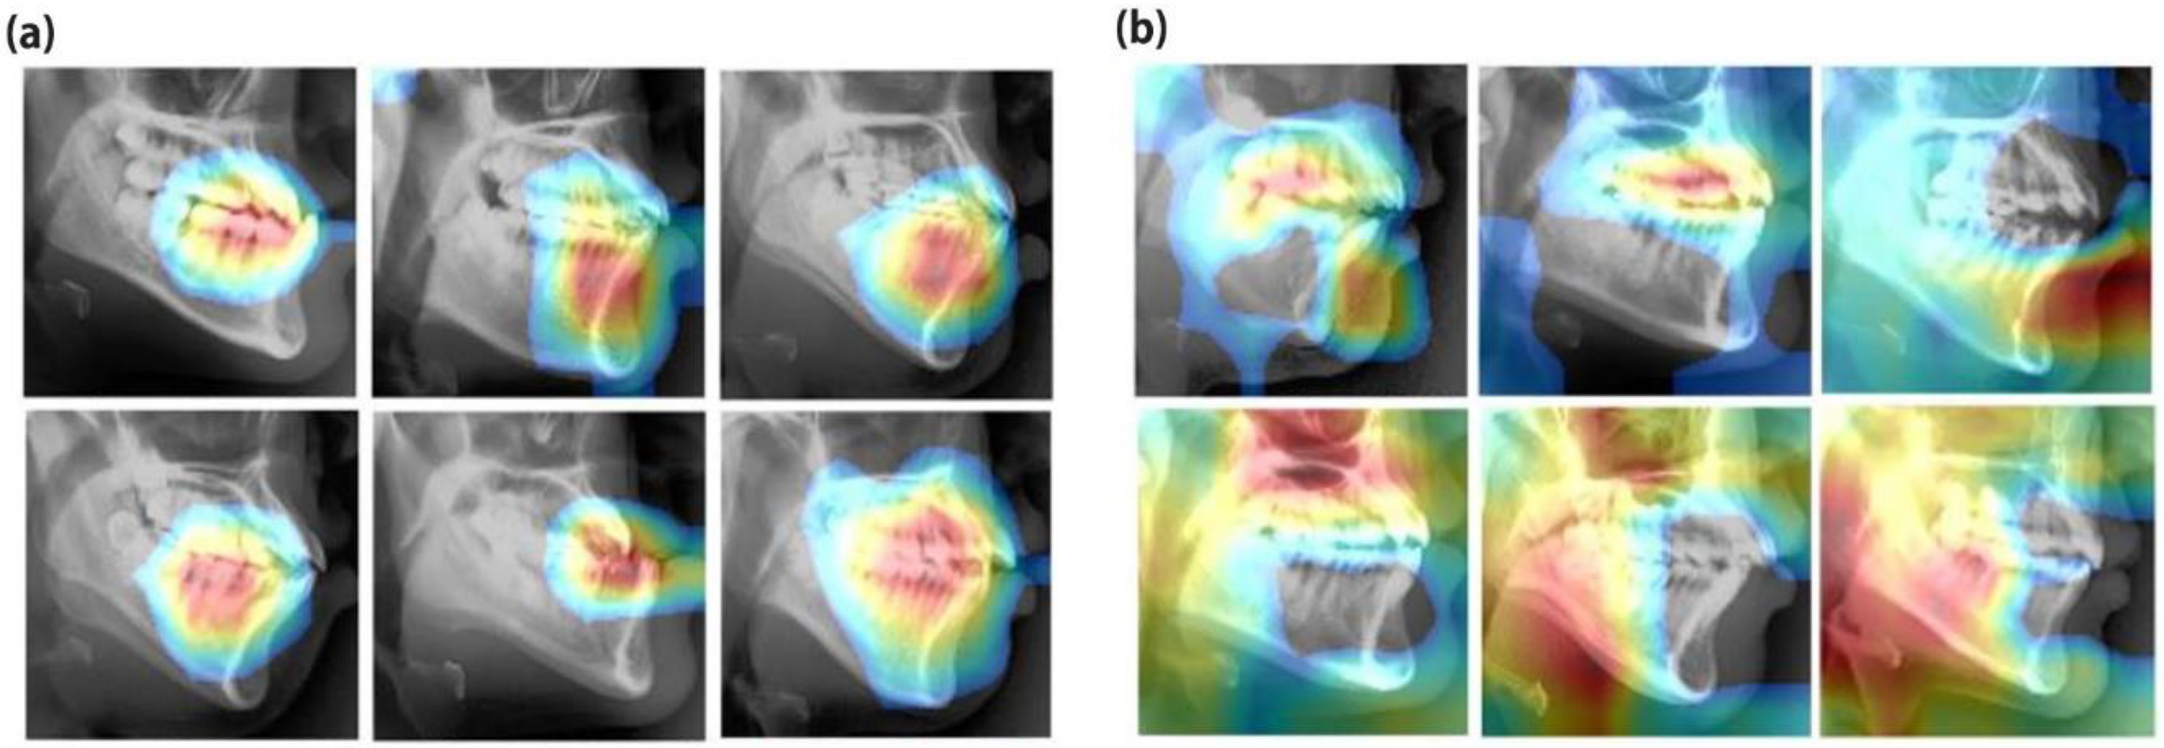

- Selvaraju, R.R.; Cogswell, M.; Das, A.; Vedantam, R.; Parikh, D.; Batra, D. Grad-CAM: Visual explanations from deep networks via gradient-based localization. arXiv 2016, arXiv:1610.02391. [Google Scholar]